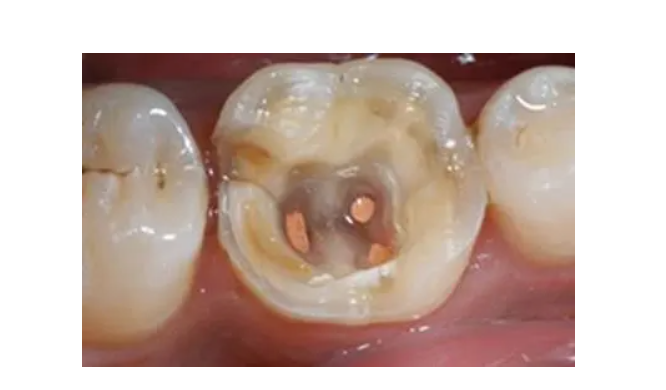

根管治疗是一种常见的牙齿治疗方法,适用于牙髓组织受到感染或损伤的情况。然而,对于很多人来说,进行根管治疗会引起一些不适和疼痛。那么,根管治疗第二次还会疼吗?下面就让我们来探讨一下。

在了解根管治疗是否会疼痛之前,我们需要先了解一下根管治疗的原理。根管治疗的目的是清除牙齿内的感染物质,填充根管空腔,以防止感染再次发生。在进行根管治疗的过程中,牙医会使用镍钛文件从口腔良好进入到牙根的内部,然后将牙髓组织完全清除。这个过程可能会引起疼痛的感觉。

通常情况下,在进行根管治疗第二次时,疼痛感可能会比第一次少一些。因为在第一次治疗后,感染和炎症已经得到了消除,所以第二次治疗只需要修复和填充根管空腔。但是,由于每个人的反应和耐受能力不同,有些人可能仍然会在根管治疗过程中感受到疼痛。